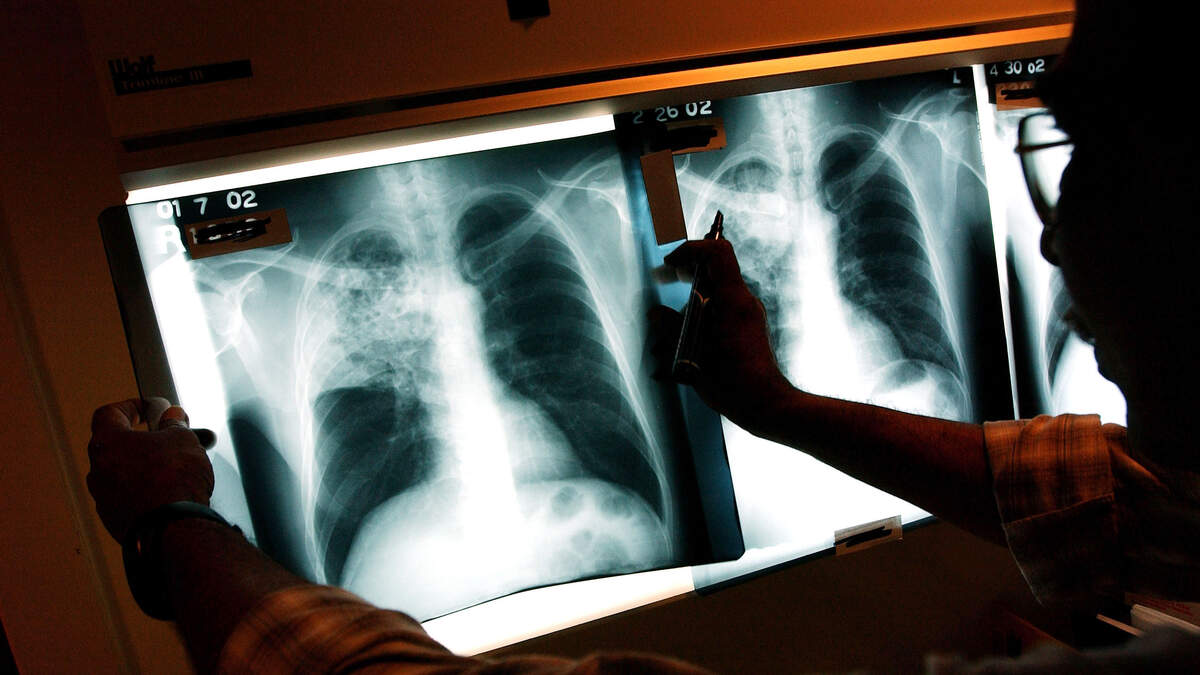

Ring Lost 5 Years Ago Found In His Lung!

Joey Lykins lost his nose piercing five years ago, couldn't find it anywhere. He finally gave up looking and decided to buy a new one and move on in life. The other night he woke up with a terrible cough and had a hard time breathing. He went to the hospital, they took a chest X-ray and guess what.... his lost septum ring was sitting in one of his lungs. He says, "The doctor came in and showed me the X-ray picture and said, ‘Does this look familiar?' I was like, ‘You’ve got to be kidding me! I’ve been looking for that.'" Doctors performed emergency surgery and were able to remove the piercing.